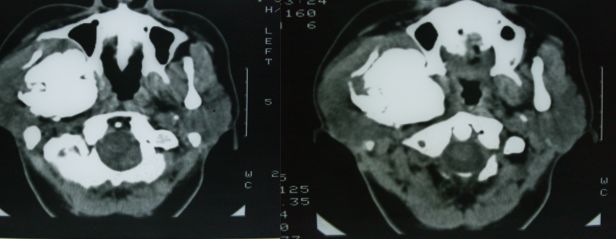

标题: CT12916:求助 F/44 右聂部肿痛一年余 [打印本页]

标题: CT12916:求助 F/44 右聂部肿痛一年余

是什么肿瘤

右侧下颌骨升支单骨病变,考虑非骨化纤维瘤可能。图片模糊,期等结果。